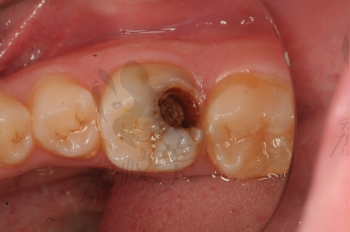

牙齒疼痛是常見(jiàn)的口腔問(wèn)題之一,而牙爛了個(gè)大窟窿晚上痛更是讓人難以忍受,這種情況不僅影響生活質(zhì)量,還可能引發(fā)其他口腔疾病,本文將為您解析牙爛窟窿的原因,并探討應(yīng)對(duì)方法和預(yù)防措施。

牙爛窟窿的原因

1、齲齒:齲齒是牙齒爛掉的主要原因之一,長(zhǎng)期不注意口腔衛(wèi)生,細(xì)菌滋生導(dǎo)致牙齒逐漸腐蝕。

2、牙周?。貉乐懿】赡軐?dǎo)致牙齒周圍組織感染,進(jìn)而引發(fā)牙齒爛掉。

3、牙齒外傷:牙齒受到外傷,如撞擊等,可能導(dǎo)致牙齒結(jié)構(gòu)破壞,出現(xiàn)窟窿。

4、長(zhǎng)期口腔健康問(wèn)題忽視:長(zhǎng)期忽視口腔健康,不進(jìn)行治療,可能導(dǎo)致牙齒爛掉。